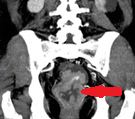

Κόκκινα βέλη. Παχυσμένο τοίχωμα ορθού. Πράσινο βέλος. Περιτονία του μυός ανελκτήρα του πρωκτού (Ευγενική παραχώρηση Dr. V. Penopoulos)